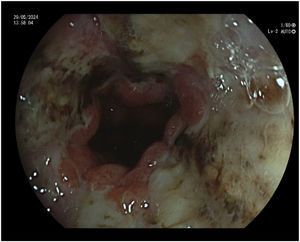

Supportive treatment was prescribed during hospitalisation: pantoprazole 40 mg once daily, metoclopramide 10 mg every 8 h, ondansetron 4 mg every 8 h, dexamethasone 4 mg once daily, and intravenous fluid therapy. The following imaging studies were performed: a cranial computed tomography (CT) scan, which ruled out metastatic brain disease; and chest, abdomen, and pelvis CT scans, which ruled out tumour progression. An upper endoscopy was also performed, revealing oesophageal mucosa covered with fibrin and necrotic areas (Fig. 1), predominantly in the distal oesophagus, and necrosis in the duodenal bulb. These findings are consistent with AON. The gastrointestinal department assessed the patient and concluded that there were no endoscopic or surgical treatment options, and that supportive care was the only feasible approach.